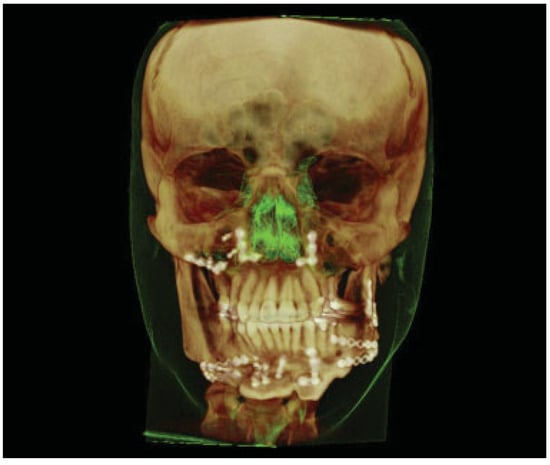

:Case Report